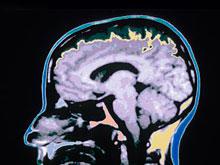

Полностью восстановиться после черепно-мозговой травмы невозможно, говорят эксперты

И спустя много лет она может стать причиной развития слабоумия. Сотрудники Имперского колледжа Лондона обнаружили в мозге людей, казалось бы, давно оправившихся после травмы головы, амилоидные бляшки, характерные для болезни Алцгеймера. В исследовании...